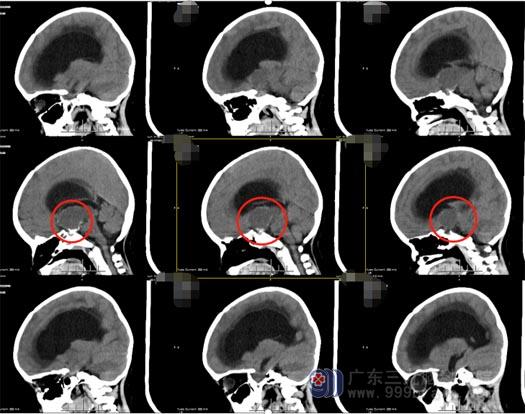

于是,他们联系了之前的主管医生——神经外五科副主任卢建侃,卢建侃看过小妍的头颅MR检查报告后认为:孩子脑积水严重,应尽快手术治疗。小妍父母一点不敢耽搁,赶紧带着孩子来到广东三九脑科医院。我院头颅CT提示:鞍上占位性病变、脑积水。这是的小婷已经是嗜睡状了。

鲁明副院长和神经外五科王国良主任带领治疗团队进行了详细的病例讨论:患儿嗜睡状,哭声间断,呕吐,头颅CT提示鞍内、鞍上、三脑室巨大占位:颅咽管瘤?梗阻性脑积水。患者脑积水严重,家属同意后急诊给予脑室外引流;次日行鞍内、鞍上、三脑室巨大占位切除术,术中见肿瘤起源于垂体柄中央,瘤内减压后沿着肿瘤的包膜切除肿瘤,患者双侧下丘脑被肿瘤侵犯,予肿瘤全切,手术过程顺利。